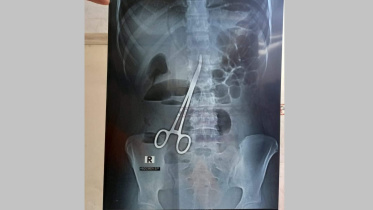

পেটে কাঁচি রেখেই সেলাই, ৬৪৩ দিন পর অপসারণ

ফরিদপুরে বঙ্গবন্ধু শেখ মুজিব মেডিকেল কলেজ হাসপাতালে এক তরুণীর পেটে অস্ত্রোপচারের সময় চিকিৎসকের রেখে দেওয়া একটি কাঁচি ৬৪৩ দিন পর আবার অস্ত্রোপচার করে বের করা হয়েছে।